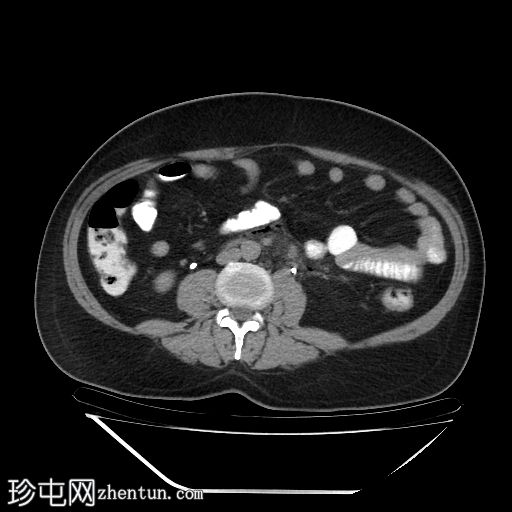

冠状位增强扫描(门静脉期)

降结肠和乙状结肠可见多个小憩室,伴有少量小(亚厘米级)区域淋巴结肿大。周围脂肪和肠壁无明显增厚。

远端降结肠后壁可见一小(<15 mm)、局限性空腔,内含气泡,伴有不规则肠壁强化和轻度邻近肠系膜脂肪条索状改变。

未见脓肿、腹水、弥漫性气腹,提示IA期复杂性急性穿孔性憩室炎(局部穿孔)。

临床表现符合IA期复杂性急性穿孔性憩室炎(局部穿孔)。